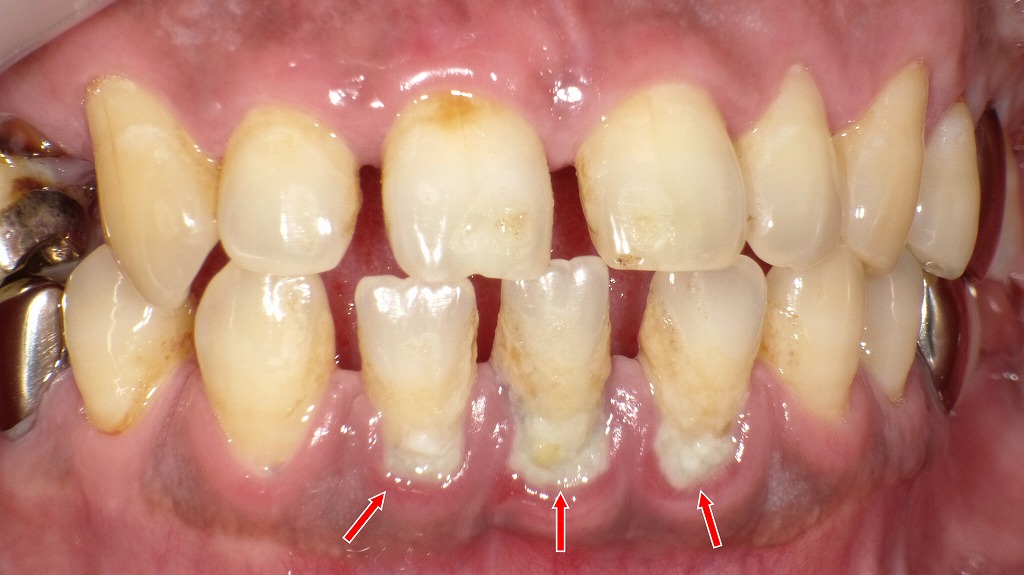

画像では、下顎前歯の根元に 大量のプラーク(歯垢) と 固まった歯石 が付着しています。

特に赤矢印の部分は歯石が厚く沈着し、歯ぐきが腫れて赤くなっているため、歯周病が進行した状態が見て取れます。

- 歯石が歯ぐきの中に入り込み、炎症(歯肉炎〜歯周炎)を悪化させています

- プラークが付着したまま時間が経つと、唾液中の成分と結びついて歯石となり、歯磨きでは取れない状態になります

- 歯石は表面がザラザラしており、新しいプラークがさらに付きやすい悪循環に陥ります

- 前歯の根元が大きく露出しているため、歯周病による骨の吸収も疑われる状況です

この画像のように歯石が大量に付いてしまう方は、

夜の歯磨きが不十分な傾向があります。

この画像のような状態を防ぐには――

- 夜の歯磨き+フロス/歯間ブラシ

- プラークが溜まりやすい下顎前歯の裏側は意識的に時間をかける

- すでに歯石が多い場合は、**歯科医院での歯石取り(スケーリング)**が必要